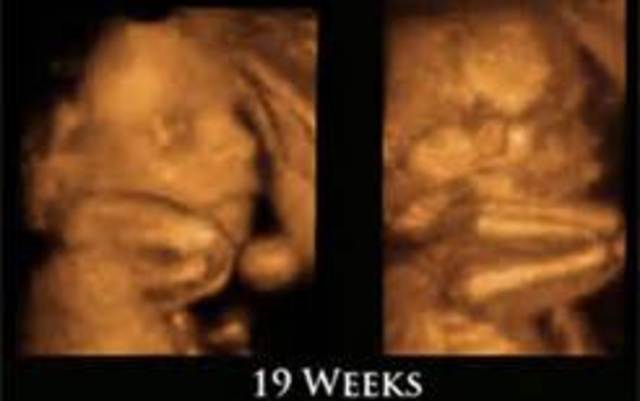

• Week 19

Week 19

I got it fromIf baby is female the uterus starts to develop, the vagina, uterus, and fallopian tubes are in place. Females have a limited supply of eggs in their lifetime. At this point your daughter will have 6 million eggs. This amount decreases to approximately one million by birth. If it's a boy, the genitals are distinct and recognizable. Even if the sex looks obvious, ultrasound operators have been known to make mistakes.